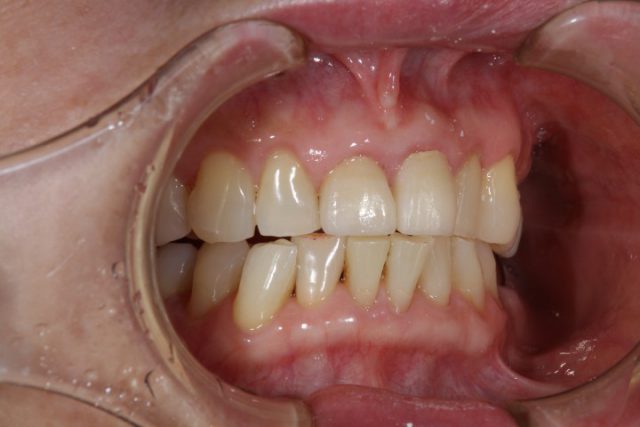

施術前

前歯の被せ物の取り替える場合はまわりの歯との色味をどこまで自然に合わせてくるかが重要になります。せっかく被せ物をやり直すからできるだけ白いものと思ってしまいそうですが、まわりの歯と色味が合わないと白くても違和感が出てきてしまいます。